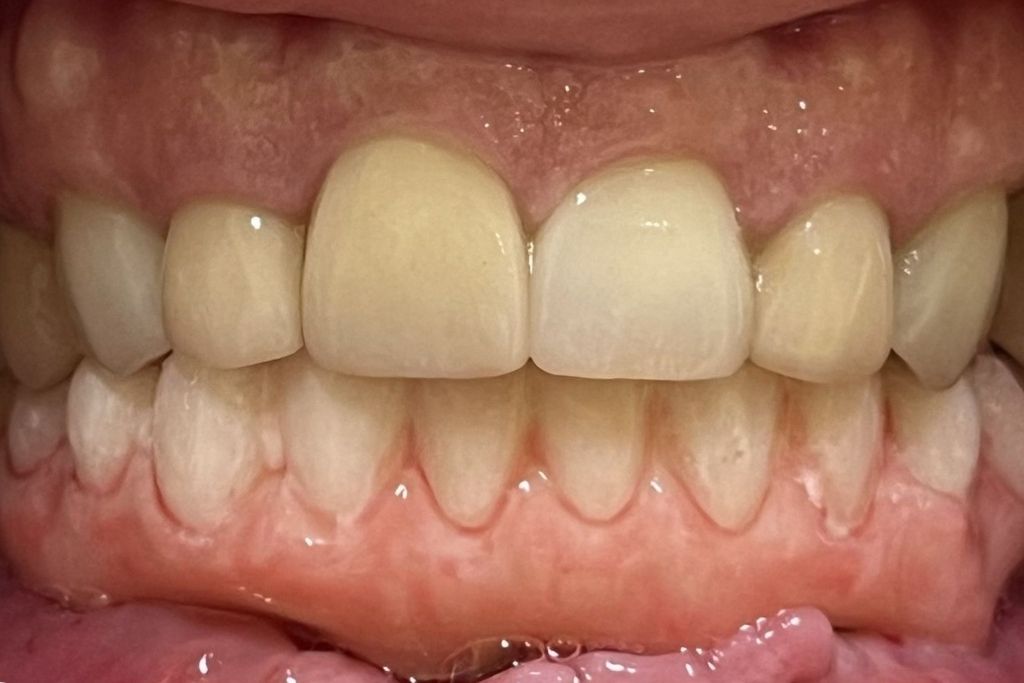

All on X dental implants are designed to replace a full upper or lower set of teeth with a secure, fixed solution that looks and feels natural. This approach supports an entire arch of teeth using dental implants, helping restore comfort, function, and confidence in everyday life. All on X treatment may be completed using All on 4 or All on 6, depending on what your mouth needs to achieve proper stability and long term support.

Regardless of whether All on 4 or All on 6 is recommended, the goal of All on X dental implants remains the same: to provide a stable, comfortable set of teeth that looks natural and supports lasting oral health.

Patients who complete All on 4 treatment often notice meaningful changes in their everyday comfort and confidence. Eating, speaking, and smiling tend to feel more natural again, and the stability of the restored arch helps make daily routines easier. Many patients appreciate that this approach can simplify long term maintenance while giving them a strong, dependable smile that supports a better quality of life moving forward.